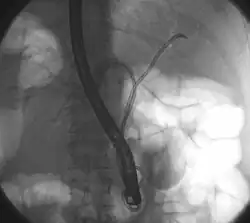

![]() опухоль Клатскина во время РХПГ. В левом и правом желчных путях. В обе половины вводили трубку с контрастом. в области слияния хорошо виден недостаток контраста. | |